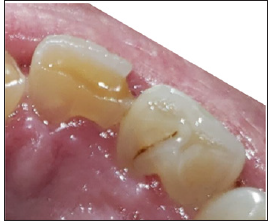

Radiograph and intraoral examinations reveal worn-down teeth [#s 07, 08 and 09] (Figures 1-5) as well as tooth gemination [# 10] (Figures 1-7). The evaluation of periapical radiographs taken of teeth [#s 07, 08, 09, and 10] presents with no evidence of periapical radiolucency. Tooth [# 08], however, shows significant internal root resorption to the mid-way and calcified the apical half of the root to the apex. Tooth [# 09] also shows a significant external/internal root resorption which is more evident on the distal aspect of the tooth, (Figure 7). Both merged segments of geminated tooth [#10] (Figure 6), shows almost completely calcified root canals to the apex. This calcification is also evident in tooth [# 07] (Figure 7).

Figure 5:Linguo-incisal view geminated / double tooth # 10 heavy attrition on incisal edge / fracture on Disto-Facio-Linguo-Incisal (DFLI) of tooth # 09.

Figure 6: Germinated/Double tooth with completely calcified root canals.

Figure 7:Teeth #s 08 & 09 radiographic evidence of external / internal root resorptions & partially calcified root canal.